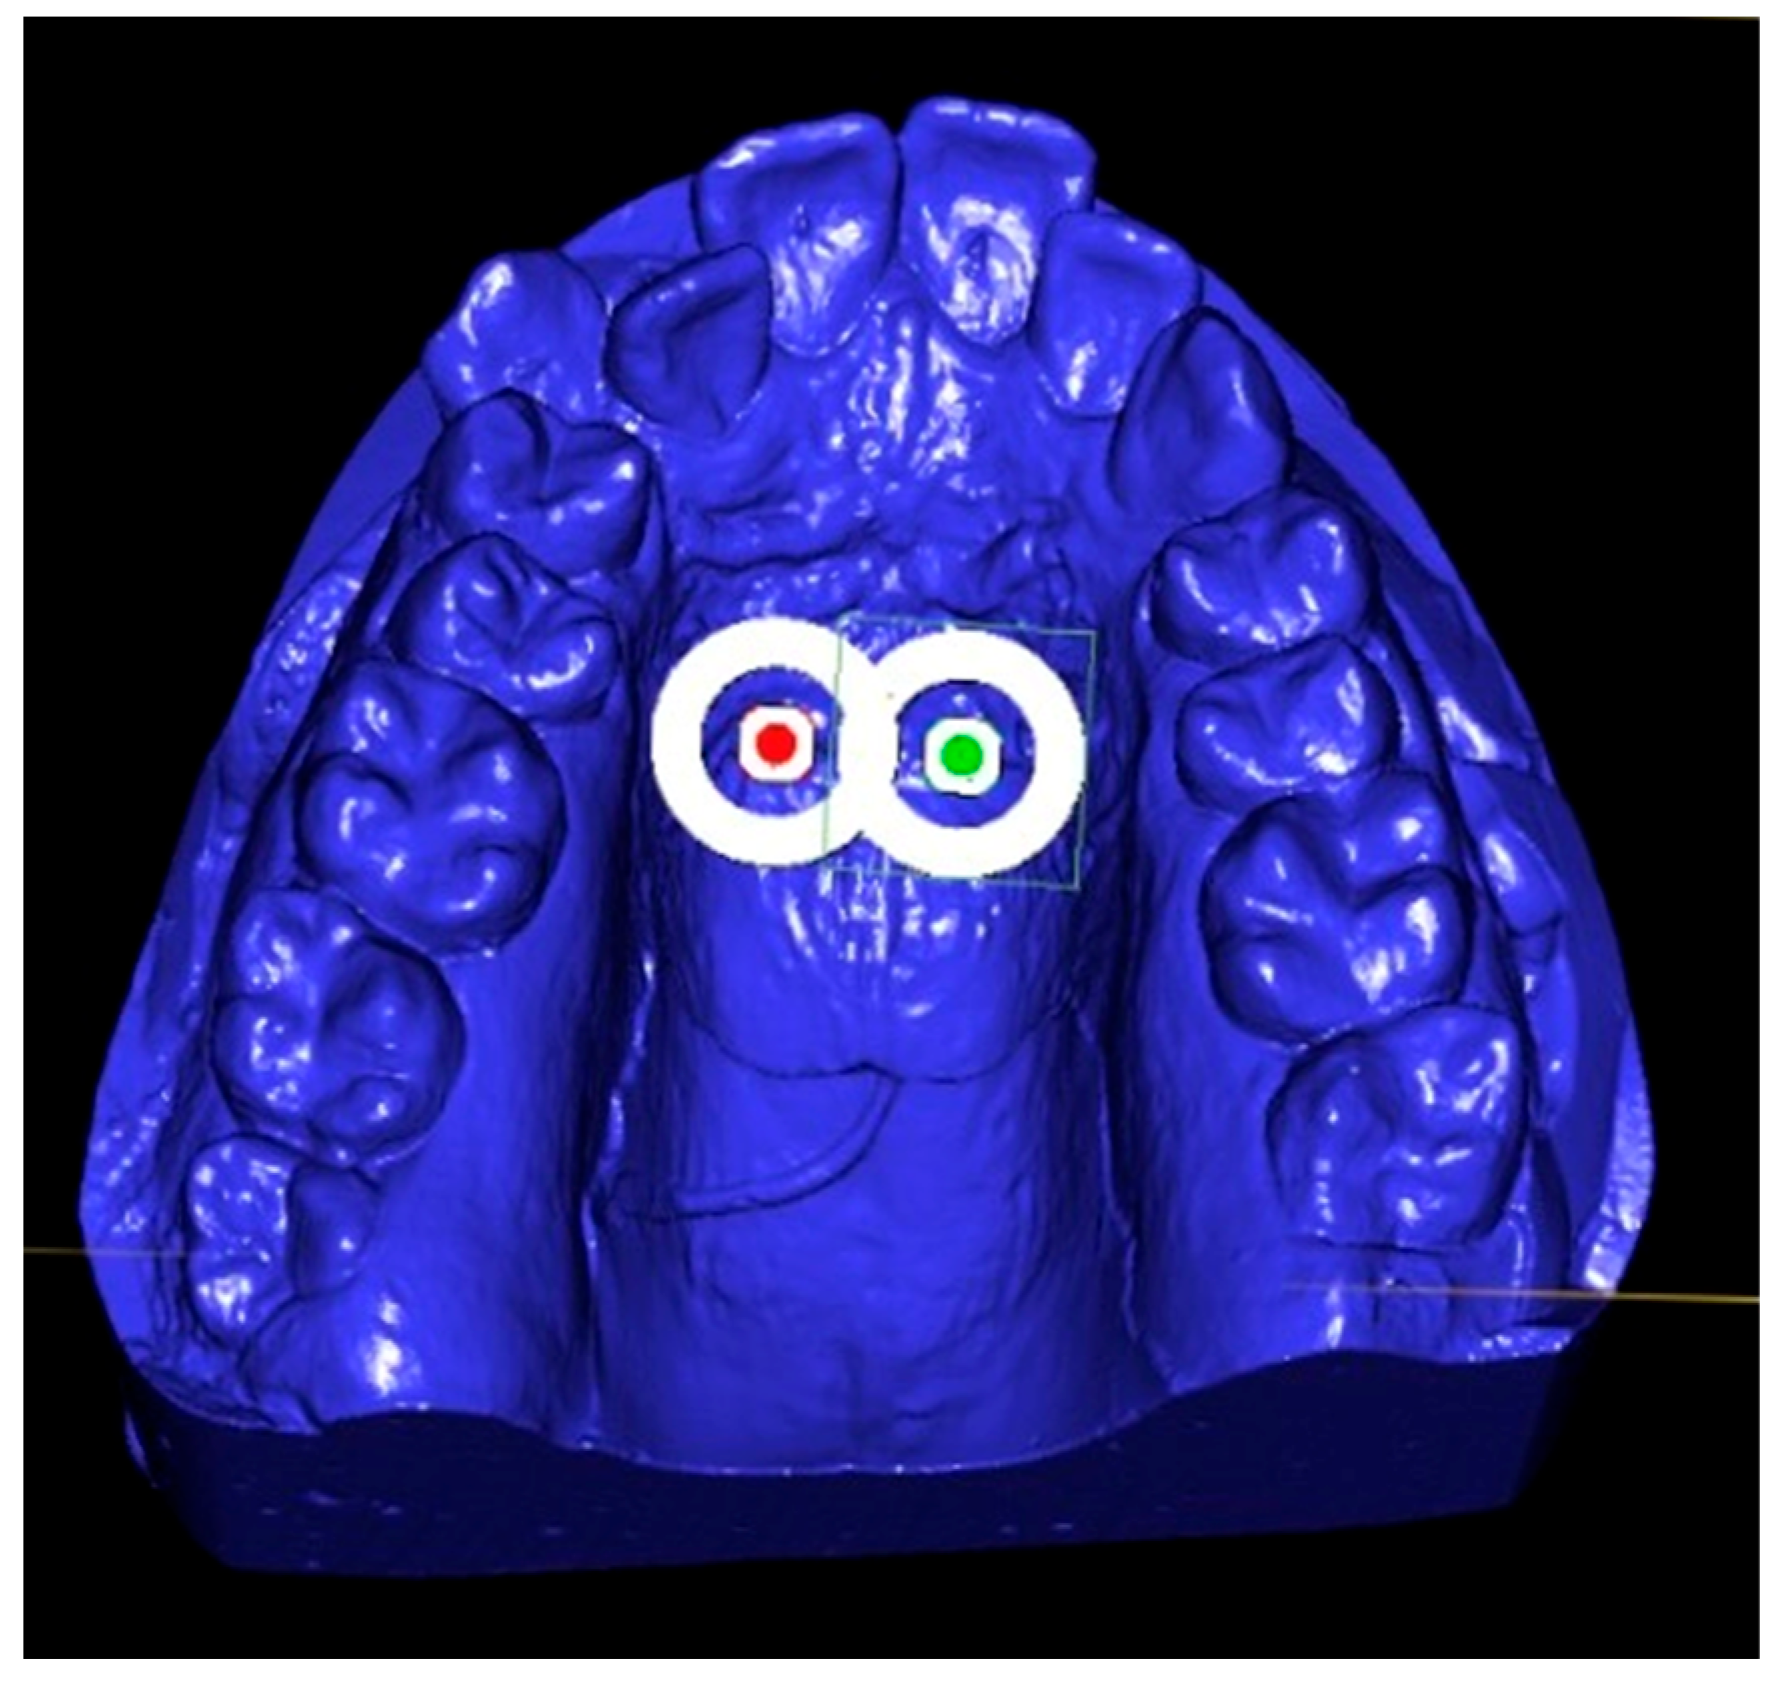

- The Benefit system introduced by Dr. Benedict Wilmes et al. in 2008 (Benefit system, PSM Medical Solutions, Tuttlingen, Germany) that uses two mini-implants placed in the anterior zone of the palate behind the second palatal rugae and arms on each side soldered to the molar bands [27]. An example of a 3D simulation for the anterior positioning of the two mini-implants, performed for a patient from our clinic, can be seen in Figure 1.